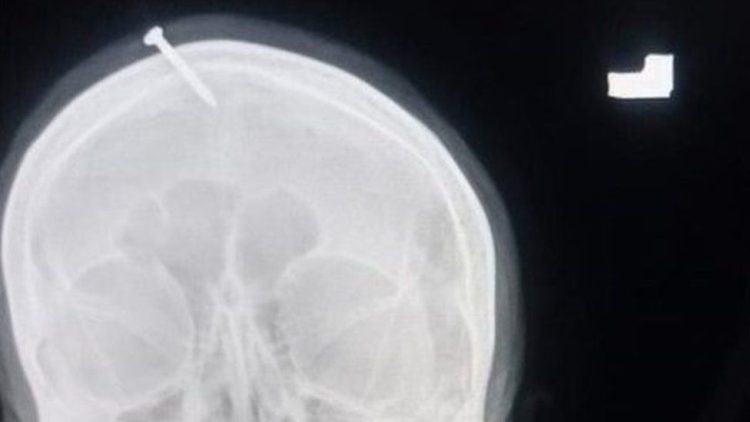

Pregnant Woman Has Nail Hammered Into Her Head to Guarantee Baby Boy

A so-called faith healer in Pakistan convinced a pregnant woman that she would give birth to a baby boy if she had a metal nail hammered into her skull. Doctors at the Lady Reading Hospital in Peshawar were shocked when they examined the head of a pregnant woman who claimed to have a two-inch-long nail […]